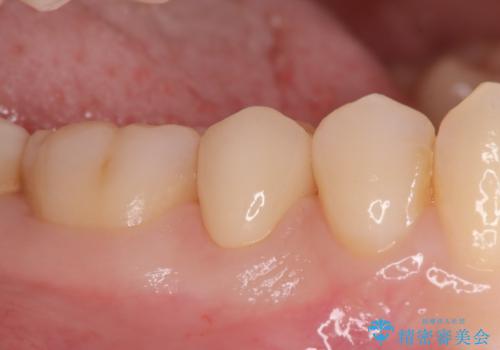

見落としやすい虫歯(コンタクトカリエス)を発見|精密診断で早期治療

- 患者様は特に痛みはなかったものの、定期検診で虫歯がないか確認したいとのことで来院されました。視診では明らかな虫歯は見当たりませんでしたが、レントゲン検査で歯と歯の間(コンタクトポイント)に虫歯(コンタクトカリエス)を発見。この部分の虫歯は初期では自覚症状が少なく、発見が遅れると治療範囲が広がることがあるため、早期に適切な治療を行う方針としました。

虫歯の部分のみを慎重に削除し、できる限り健康な歯質を残すように配慮しました。その後、強度があり適合性の高いセラミッククラウンを装着し、機能性と審美性の両方を確保。セラミックは変色しにくく、長期的な再発リスクも低減できるため、患者様にも安心していただけました。定期検診を継続することで、今後の虫歯リスクも管理していきます。